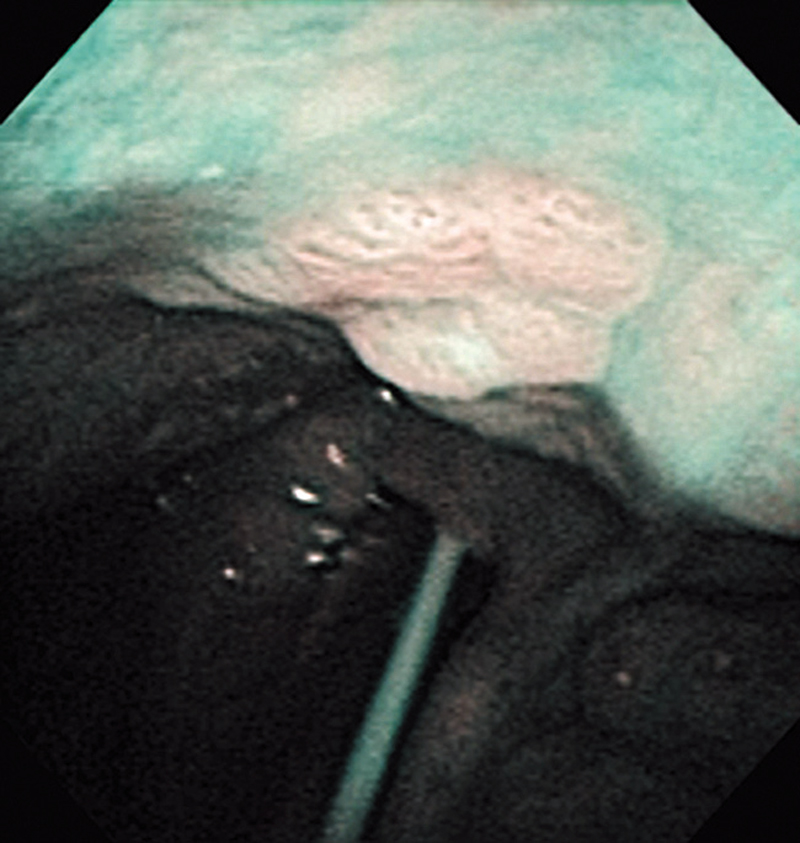

The lesion was detected in the oropharyngeal posterior wall in a laryngopharyngoscopic NBI examination during follow-up after treatment of a carcinoma in the floor of the mouth.

It was recognized under NBI as a lesion with a brownish area, and the close-up view additionally showed scattered brown dots. In the conventional white light image, the same area was seen as a reddening lesion.

The lesion was 5 x 3 mm and located on the back of the soft palate, and was diagnosed as a carcinoma in situ.